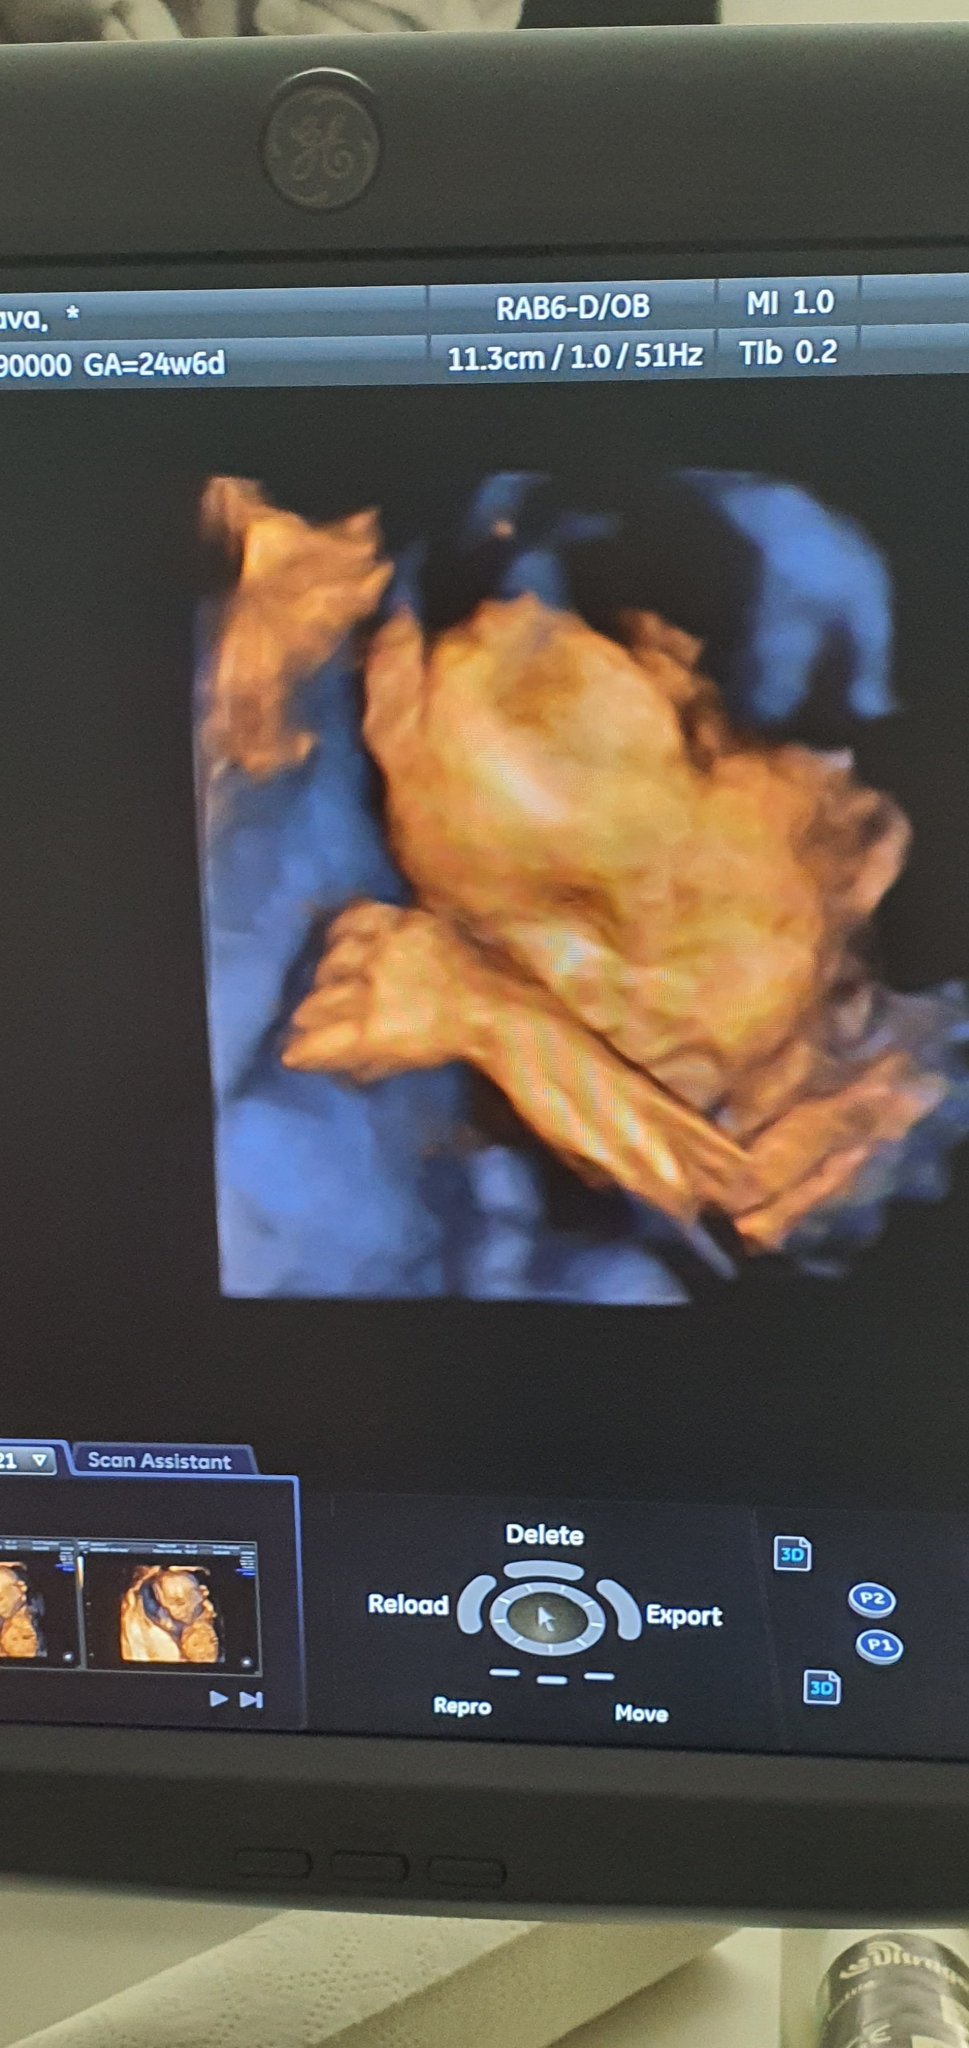

Какво представлява феталната ехокардиография и кога се препоръчва?